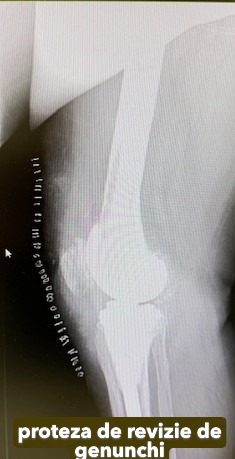

Artroplastia totală de genunchi

Artroplastia totală de genunchi constă în înlocuirea în totalitate a articulației cu o proteză cimentată, care, în prezent, este tot mai performantă.

În funcție de degradarea articulației și de calitatea țesutului osos, pot fi necesare anumite componente suplimentare: augmenturi sau stem tibial.

Dacă genunchiul este instabil, se recomandă protezele stabilizate: LCCK sau balama.

Galerie imagini cu proteze șold și genunchi tratate de dr. Chitea Claudiu Daniel